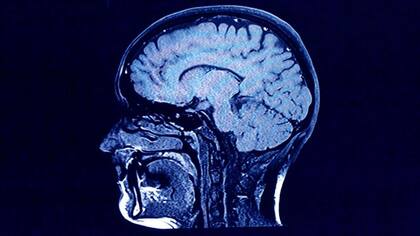

En 2013, el equipo también recurrió al pico de la bomba para observar la rotación de las células cerebrales. Durante muchos años, los investigadores asumieron que la cantidad de neuronas se consolidaba en la infancia y, de hecho, su investigación anterior ya había sugerido que ese era el caso en regiones como la corteza.

Sin embargo, mediante el uso de carbono-14 para datar las neuronas dentro del hipocampo, confirmaron que se pueden producir nuevas neuronas a lo largo de la vida adulta. Corroborada por otras investigaciones, la posible existencia de “neurogénesis adulta” ha sido uno de los descubrimientos neurocientíficos más importantes de los últimos 20 años. Esto ha sugerido nuevas vías hacia estrategias médicas que podrían prevenir la pérdida de neuronas por enfermedad o incluso aumentar la generación de nuevas.